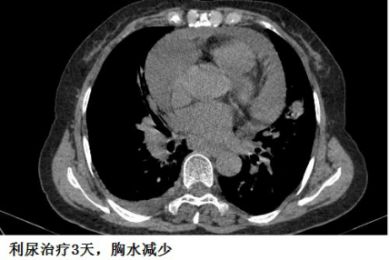

下面的图示,可以帮助大家加深印象!

另外,胸水的病因有时候很难准确判断,最初觉得可能不是心力衰竭引起的,但经验性治疗后,胸水有可能很快减少,这时候贸然按照之前的影像学资料去抽胸水,有可能“干抽”。

为什么?每个人不一样!有些患者的胸腔积液,特别是心力衰竭引起的胸腔积液,有可能几天就吸收了,一不小心,就“干抽”了。病因可逆的胸水,都要谨慎,要参考最近1~2天的资料。

这个患者的胸水,应该是心包积液导致静脉回流受阻,体循环淤血引起的。利尿治疗后,胸水减少。